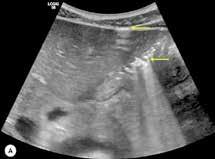

A las 36 horas de vida presenta nuevo empeoramiento respiratorio, se solicita estudio completo y se realiza punción lumbar (a pesar de paráme tros infecciosos negativos en la analítica). Se obtiene líquido purulento y se procede a escalada de tratamiento a ceftriaxona y ampicilina (mantiene tratamiento durante 7 y 3 días respectivamente, no aislándose microorga nismos en muestras de líquido cefalorraquídeo ni hemocultivos). Se repite la radiografía de tórax en la que se evidencia neumotórax de nueva apa rición e imagen sugestiva de neumomediastino. Ante estos hallazgos, se solicita TC de tórax que confirma el diagnóstico y descarta la existencia de causas desencadenantes (Figura 2). Se mantienen requerimientos de VMNI durante 4 días más, siendo finalmente posible la desescalada gradual a oxigenoterapia con gafas nasales durante 4 días. Se consigue retirada del soporte respiratorio de manera completa pasados 8 días, realizando un control con TC de tórax a los 9 días de vida (Figura 3) que muestra mejoría significativa acompañándose de una recuperación clínica completa.

Figura 2. (Izq.) radiografía de tórax en proyección AP a las 36 horas de vida donde se objetiva neumotórax de nueva aparición (flechas azules) y una zona de hiperclaridad alrededor de la silueta cardíaca que sugiere importante neumomediastino (estrellas amarillas). (Der.) TC de tórax sin contraste intravenoso en ventana de pulmón que confirma la presencia de neumomediastino (estrella amarilla). Se objetivan focos de consolidación periféricos y bandas lineales de densidad aire paralelas y adyacentes a las vainas broncovasculares (flechas amarillas).